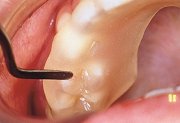

| スプリントレジンLCを歯列に圧接し外形を整えた後軽く咬合させ、対合する歯列咬合面の圧痕を印記する。 |

| ハンドインスツルメントを用いて咬合接触点をできるだけ平坦に仕上げる。また、咬合接触の不足部分にはスプリントレジンLCの小片を圧接追加し、咬合させる。 |